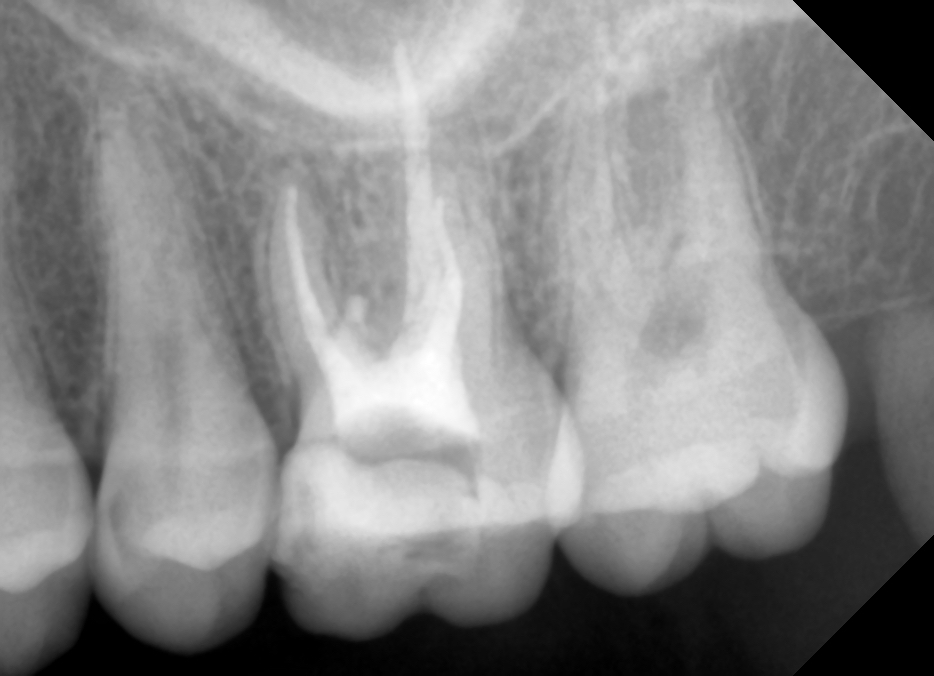

După aceea, tratamentul de canal a urmat etapele clasice: s-a efectuat îndepărtarea obturatiei de canal anterioare de pe toate canalele, curățarea mecanică și antiseptică a canalelor radiculare, urmând apoi obturarea finală a canalelor. (Figura 6) Toate acestea s-au desfășurat sub controlul constant la microscop, asigurându-se că fiecare etapă a fost realizată cu succes.

Rădăcina și canalele au fost apoi sigilate cu material compozit (Figura 7), s-a efectuat radiografia de control (Figura 8) și apoi pacientul direcționat înapoi la medicul referal pentru a finaliza restaurarea coronară. Astfel, tratamentul de canal finalizat într-un mod precis și eficient a contribuit la restabilirea sănătății orale a pacientului și la evitarea complicațiilor viitoare.